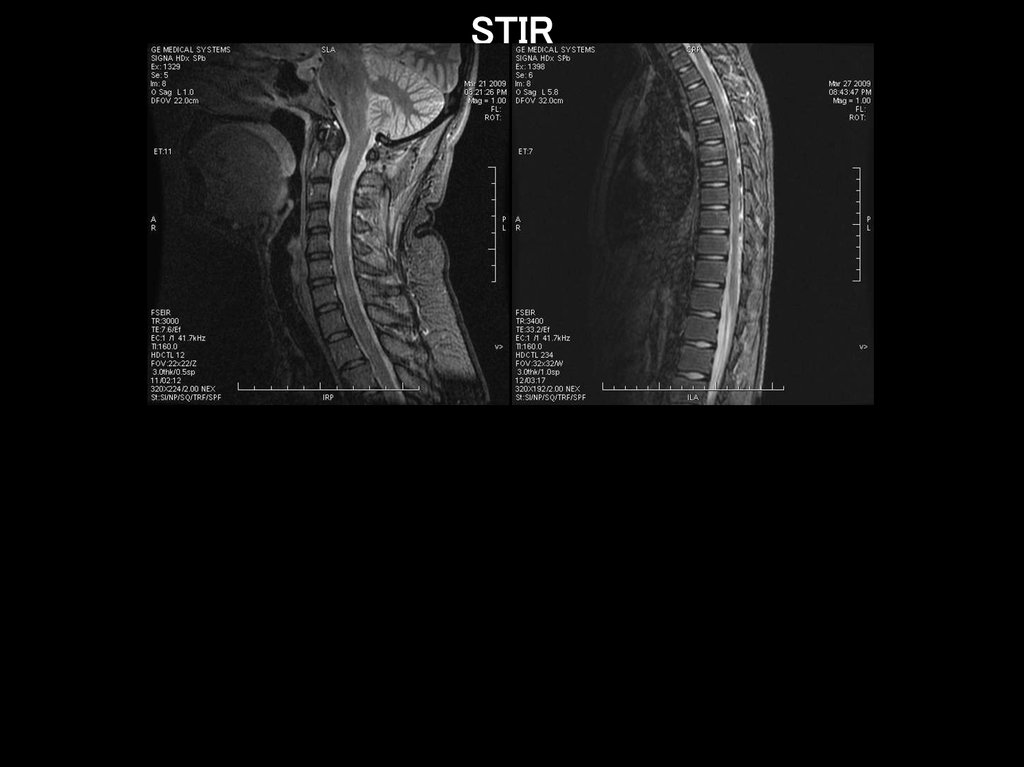

STIR